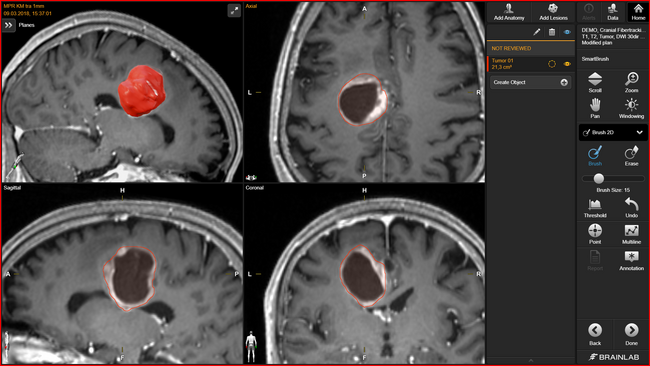

頭蓋内腫瘍の輪郭描出の自動化を実現2025年9月、ブレインラボ株式会社(本社:東京都港区)は、手術計画用および放射線治療計画ソフトウェアBrainlab(R)Elementsのアプリケーションの一つで...